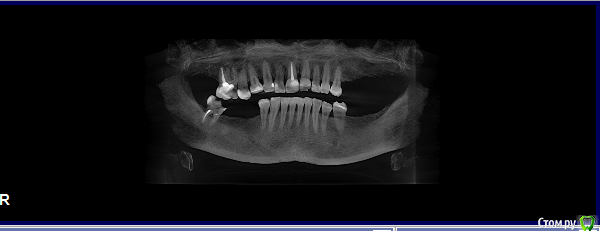

elesilchenko@yandex.ru Опубликовано 18 октября, 2016 Поделиться Опубликовано 18 октября, 2016 Здравствуйте! Подскажите, пожалуйста, возможна ли дентальная имплантация на НЧ без применения костной пластики? И возможно ли спасти зубы с кистами на ВЧ ?Результаты КТ: http://files.mail.ru/1F70A64348084F03ACC722DA9E76BD2B Ссылка на комментарий

elesilchenko@yandex.ru Опубликовано 18 октября, 2016 Автор Поделиться Опубликовано 18 октября, 2016 Добрый вечер! Я в процессе выбора, кто предлагает базальную имплантацию внизу (ВЧ я пока не рассматриваю к имплантации) , кто съемные протезы это на НЧ. По поводу ВЧ тоже разные мнения: 1. Можно полечить, т.к. проблемы с эндодонтией 16 и 12, где небольшой воспалительный процесс.2. 16 удалить, 12 попытаться полечить. Сунус-лифтинга и костной пластики боюсь. Ссылка на комментарий

IvanK Опубликовано 18 октября, 2016 Поделиться Опубликовано 18 октября, 2016 Судя по скудной информации из скриншотов:кости , скорее всего, будет достаточно Вам нужно найти Врача, которому доверяете и довериться) Сходите на пару-тройку очных консультаций Ссылка на комментарий